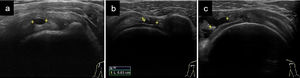

Roturas de grosor parcialLas lesiones se suelen localizar en el tercio distal o insercional del supraespinoso. El hallazgo ecográfico más importante es la presencia de un área hipoecogénica que no atraviesa todo el espesor del tendón (fig. 3a). Debemos tener en cuenta la elevada frecuencia de anisotropía en estos tendones y, por tanto, la necesidad de visualizar el defecto hipoecogénico en ambos cortes longitudinal y transversal10,11,17.

Roturas de los tendones del MR: a) Pequeña rotura del grosor parcial intrasustancia del supraespinoso en un corte longitudinal (entre 2 cruces); b) Rotura del grosor total del supraespinoso inferior a 1cm medido en eje transversal (entre 2 cruces midiendo 0,63cm); c) Rotura del grosor total de mayor tamaño pero menor de 2cm en eje transversal (entre 2 cruces), que afecta a un solo tendón.

Rotura de grosor completoLos hallazgos ecográficos son similares a los comentados en las roturas parciales. En lesiones agudas se observa una interrupción hipoecogénica o anecogénica del tendón (figs. 3b y c). En casos más avanzados la rotura es ocupada por tejido cicatricial, bursa y/o deltoides10,11,17.